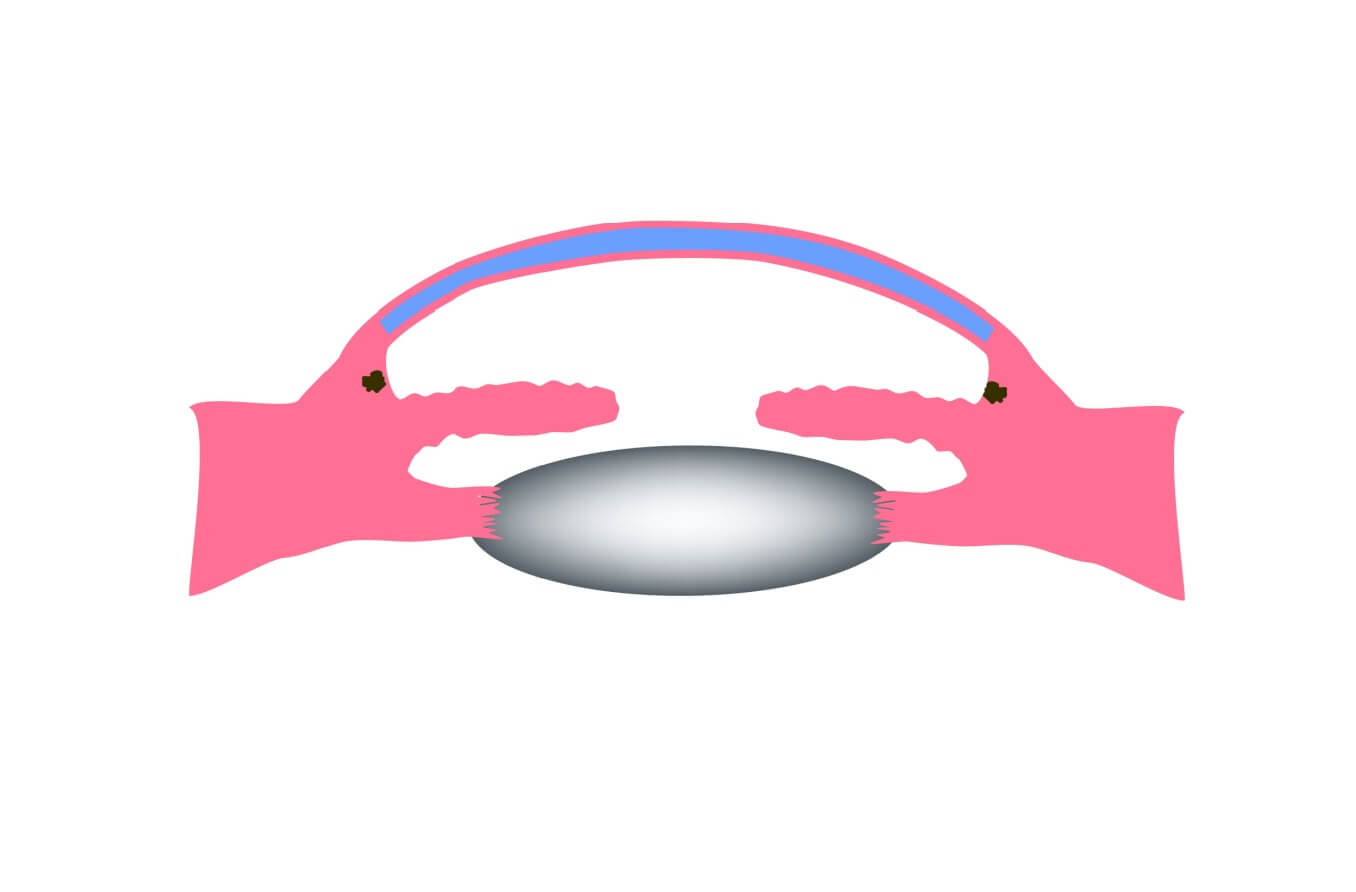

Der Ziliarkörper ist eine Struktur, die direkt hinter der Iris (dem farbigen Teil des Auges) sitzt. Eine seiner Aufgaben besteht darin, eine wichtige Flüssigkeit namens Kammerwasser zu erzeugen. Kammerwasser fließt über einen bestimmten Weg in die Vorderseite des Auges (die Vorderkammer). Dieser Weg ermöglicht es dem Kammerwasser, wichtige Nährstoffe und Sauerstoff an andere Teile des Auges, wie die Linse und die Hornhaut, zu senden.

Kammerwasser reguliert auch den Augeninnendruck (IOD) – der medizinische Name für Augendruck.

Sobald das Kammerwasser seinen Lauf genommen hat, fließen 80-90 % davon durch ein schwammartiges Gewebe ab, das Trabekelnetzwerk genannt wird. Dieses Netzwerk befindet sich am unteren Ende des Abflusswinkels des Auges, wo die Hornhaut auf die Iris trifft. Bei einem gesunden Auge ist dies ein ständiger Prozess. Der Ziliarkörper produziert ständig Kammerwasser, und das Kammerwasser fließt ständig durch das Trabekelnetzwerk ab.

Beim primären Offenwinkelglaukom erscheint der Abflusswinkel normal und klar. Aber oft gibt es tiefer im Kanal eine Verstopfung – denken Sie an ein verstopftes Rohr, das den Abfluss des Wassers aus Ihrem Spülbecken verhindert.

Experten gehen davon aus, dass sich im Trabekelnetzwerk ein Problem entwickelt, das den Flüssigkeitsdurchfluss verlangsamt. Mit der Zeit steigt der Augeninnendruck, weil der Kammerwasserabfluss nicht mit der Produktion Schritt halten kann.

Beim Engwinkelglaukom kann dies viel schneller passieren. Dieser Typ entsteht normalerweise, wenn der Druck hinter der Iris die Iris nach vorne drückt. Die Iris blockiert dann einen Teil oder den gesamten Abflusswinkel.

Wenn sich der Winkel verengt, begrenzt dies die Flüssigkeitsmenge, die zum Trabekelnetzwerk gelangt. Wenn sich der Winkel schließt, verhindert er, dass Flüssigkeit abfließen kann. Unter diesen Umständen wird immer noch reichlich Wasser produziert, aber nichts davon kann abfließen. Aus diesem Grund kann der Augeninnendruck sehr schnell ansteigen.